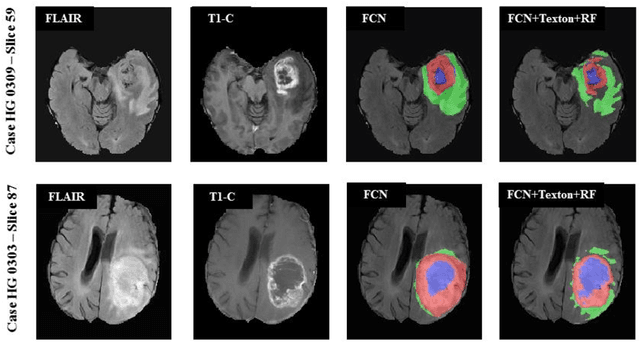

Abstract:In this paper, we propose a novel learning based method for automated segmentation of brain tumor in multimodal MRI images, which incorporates two sets of machine -learned and hand crafted features. Fully convolutional networks (FCN) forms the machine learned features and texton based features are considered as hand-crafted features. Random forest (RF) is used to classify the MRI image voxels into normal brain tissues and different parts of tumors, i.e. edema, necrosis and enhancing tumor. The method was evaluated on BRATS 2017 challenge dataset. The results show that the proposed method provides promising segmentations. The mean Dice overlap measure for automatic brain tumor segmentation against ground truth is 0.86, 0.78 and 0.66 for whole tumor, core and enhancing tumor, respectively.

Abstract:In this paper, we propose a novel learning based method for automated segmenta-tion of brain tumor in multimodal MRI images. The machine learned features from fully convolutional neural network (FCN) and hand-designed texton fea-tures are used to classify the MRI image voxels. The score map with pixel-wise predictions is used as a feature map which is learned from multimodal MRI train-ing dataset using the FCN. The learned features are then applied to random for-ests to classify each MRI image voxel into normal brain tissues and different parts of tumor. The method was evaluated on BRATS 2013 challenge dataset. The results show that the application of the random forest classifier to multimodal MRI images using machine-learned features based on FCN and hand-designed features based on textons provides promising segmentations. The Dice overlap measure for automatic brain tumor segmentation against ground truth is 0.88, 080 and 0.73 for complete tumor, core and enhancing tumor, respectively.